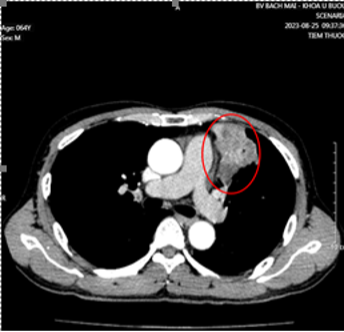

- Cắt lớp vi tính lồng ngực có tiêm thuốc cản quang:

Hình 1. Khối u kích thước 51x58x42mm thùy trên phổi trái, ngấm thuốc không đều sau tiêm (vòng tròn đỏ).